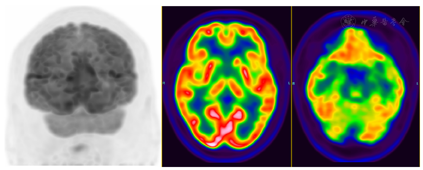

治疗半个月后,患者夜间睡眠不自主运动及言语增多现象均缓解,白天肢体不自主运动次数减少。复查血清抗LGI1抗体1∶100,抗IgLON5抗体1∶10,抗体滴度较前下降。3个月后随访:睡眠已恢复正常,左上肢不自主运动消失,记忆力明显好转。治疗3个月后复查18F-FDG PET/CT示原双侧尾状核体部、左侧尾状核头、双侧壳核、左侧颞叶内侧(包括左侧海马-杏仁核复合体)、左侧额叶内侧及左侧岛叶代谢增高均基本消失;右侧尾状核头及左侧颞叶内侧代谢较对侧减低(图3)。

治疗半个月后评估,患者夜间睡眠不自主运动及言语增多现象均缓解,白天肢体不自主运动次数减少,血清抗LGI1抗体1∶100,血清抗IgLON5抗体1∶10,抗体滴度较前下降。治疗后3个月随访:睡眠已恢复正常,左上肢不自主运动消失,记忆力明显好转。治疗后3个月复查PET/CT示原双侧尾状核体部、左侧尾状核头、双侧壳核、左侧颞叶内侧(包括左侧海马-杏仁核复合体)、左侧额叶内侧及左侧岛叶代谢增高均基本消失;右侧尾状核头及左侧颞叶内侧代谢较对侧减低。